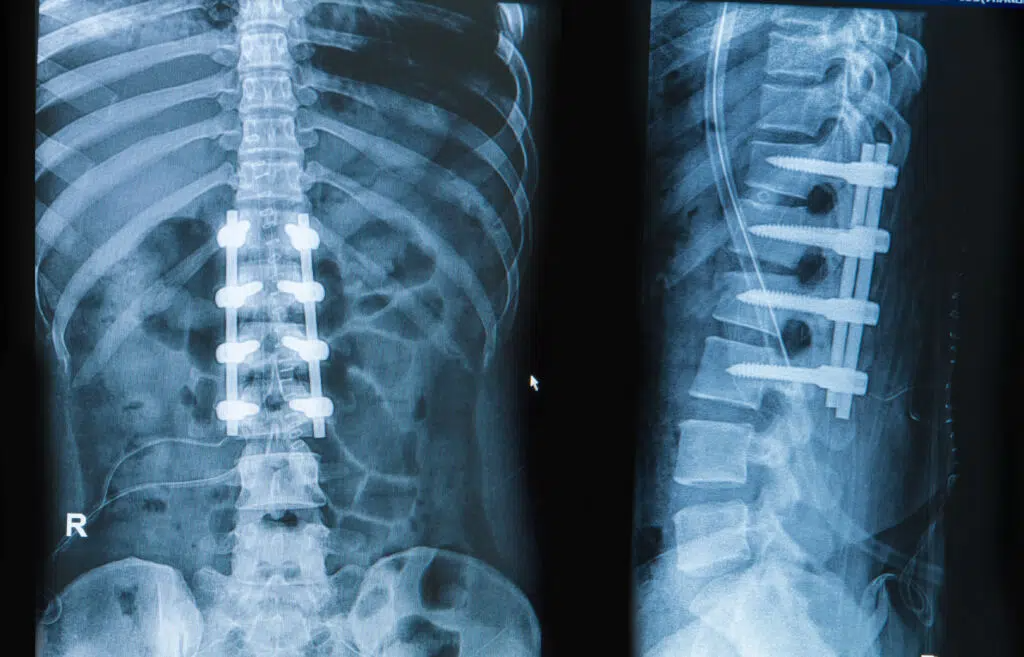

A spinal fusion procedure is a surgery to permanently join two bones together so there is no longer movement between them. We offer minimally invasive spinal fusion procedures that typically result in scars no more than 3 centimeters long.